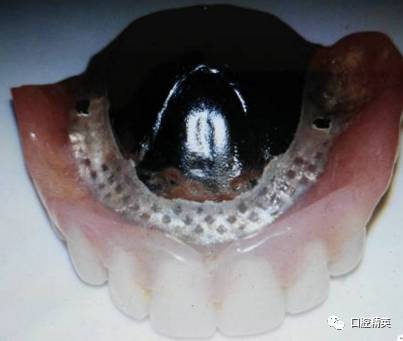

上颌旧义齿检查:张口说话咀嚼义齿脱位,无吸附力,上颌前牙过度唇倾,覆盖较深,颌平面低于上唇缘,微笑不露义齿,口角下垂,面部下1/3欠丰满。腭盖为金属基托,义齿后部未达腭小凹后2mm处。下颌金属支架义齿,33牙缺失。

上颌解剖颌胶连义齿+金属预成网。

7.采用塑料基托+金属网,增加义齿强度,缓冲下颌天然牙颌力,便于以后重衬修补。